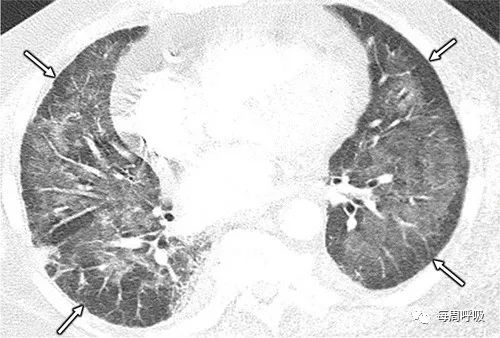

在出现肺部症状的风湿病临床患者中,最初的考虑因素通常包括 CTD-ILD 和感染(由于 DMARD 的免疫抑制)。特别是, 在没有预防措施的情况下,这些患者可能会发生肺孢子虫肺炎。接受免疫抑制治疗的炎症性肠病患者也有感染风险。炎症性肠病中潜在的弥漫性肺病并不常见(OP已被报告)。已经在使用甲氨蝶呤和其他 DMARD 治疗的患者中描述了 MIPI 的纤维化模式(图 3)。当CT 模式与NSIP一致时,它与 CTD-ILD 无法区分,并且区分通常依赖于与药物治疗的时间相关性。存在常见的间质性肺炎表现,而不是NSIP形式,有利于CTD-ILD 而不是 MIPI是纤维化的原因。在其他甲氨蝶呤引起的肺损伤病例中,主要发现是 GGO 而不是网状结构,整体外观最符合OP 模式(图 4 )。甲氨蝶呤偶尔会出现小叶中心模式,这可能代表支气管周围OP。暴露于硫唑嘌呤和 6-巯基嘌呤(图5 )时,也报告了典型的 OP 模式和小叶中心结节模式。

在风湿病和胃肠病科室的患者中,结节病样 MIPI 比其他环境中更常见,但接受免疫治疗的肿瘤患者除外。这可能与他们用免疫调节剂治疗有关,特别是 TNF-α 抑制剂。例如,TNF-α抑制剂阿达木单抗可引起结节样反应(图6)。还报道了阿达木单抗诱导的弥漫性 GGO 和其他 MIPI 模式的孤立病例(图7)。其他免疫调节药物如 IFN-α 也可产生类结节样表现(图 8)。

d40967fa15a76bbfbafad82719a40388.jpg

图 6.一名 61 岁克罗恩病男性患者在开始使用 TNF-α 抑制剂阿达木单抗治疗后出现咳嗽,阿达木单抗诱导的 MIPI。(B)轴位 CT 图像显示 MIPI 的结节病样模式,包括双侧淋巴结节(箭头)。